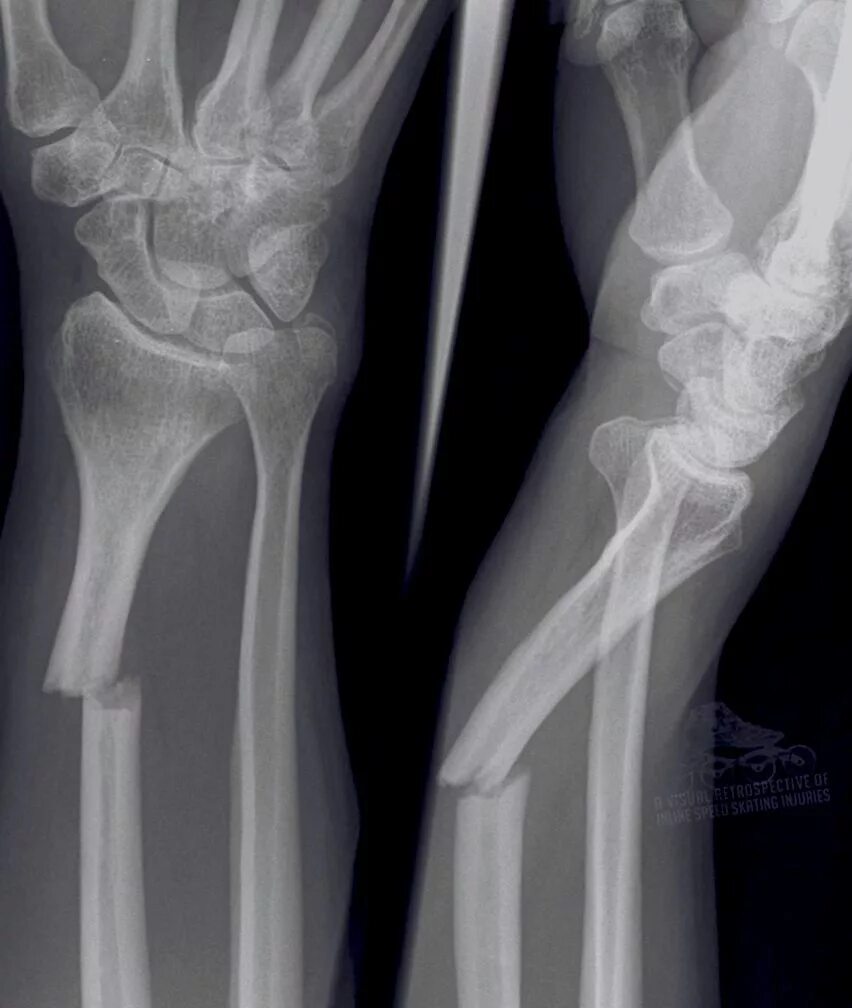

Фото переломов костей